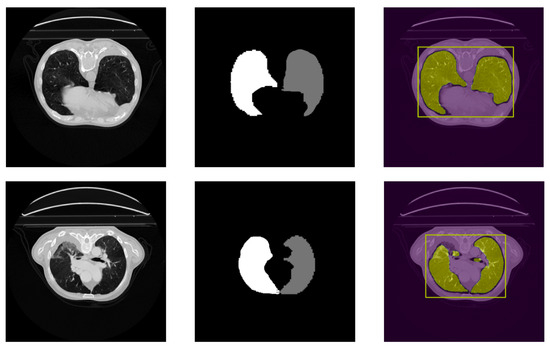

4.2. Qualitative Results

In addition to the quantitative results, we also present qualitative results to visually demonstrate the effectiveness of SALM in segmenting ROI in lung CT images. Figure 6 and Figure 7 show example segmentation results of SALM applied to 2D slices from the LUNA16 test set. These results demonstrate that SALM is able to accurately segment ROI of varying sizes and shapes.

Figure 6.

Result of segmentation with SALM-3D (left–right): original slice, original label, and segmentation result.

Figure 7.

Result of segmentation with SALM on different image sizes: segmentation on a 2D 685 × 522 image (top); segmentation on a 2D image 512 × 512 (bottom). For each image, each color represents a distinct side of the segmented lung.